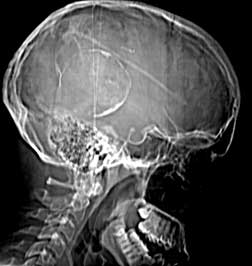

CT scout

Findings:

Round, peripherally calcified lesion (a) at the posterior aspect of the skull. Shunt tube in place (b).